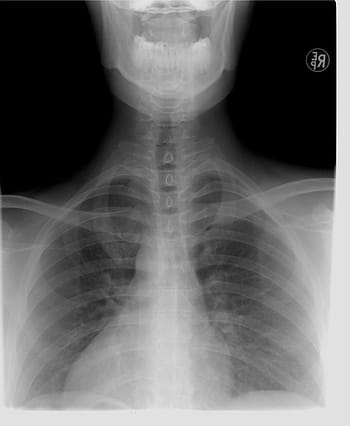

La cantidad de radiación que recibe de una radiografía de ortodoncia es de 0,010 milisierverts, que es solo un poco más que la radiación que recibe simplemente caminando al aire libre bajo el sol durante un día normal. Si está al aire libre durante un período de tiempo determinado, recibirá más radiación del sol y del entorno que lo rodea que la que recibe de uno de estos rayos X.

Aquellos que creen que las radiografías de ortodoncia no son seguras dirán que ningún nivel de radiación es seguro y que la exposición a la radiación es acumulativa, lo que significa que cuanta más radiación reciba a lo largo de su vida, mayor efecto podría tener en ti más adelante en la vida. Durante la niñez y la adultez temprana, cuando las células del cuerpo aún se están dividiendo rápidamente, es cuando la radiación puede ser más dañina para una persona. Existe la preocupación de que la radiación que se dispara directamente a la glándula tiroides del individuo sea peligrosa y eventualmente pueda provocar cáncer de tiroides (aunque no se ha establecido ningún vínculo entre las radiografías de ortodoncia y el cáncer de tiroides). Pero, nuevamente, los niveles de radiación en estos rayos X son iguales a la radiación que experimenta una persona durante un día normal. Y la mayoría de los ortodoncistas usan un delantal de plomo que protege el pecho y el cuello durante estas radiografías.

Tu ortodoncista no te está haciendo una radiografía solo por hacerte una radiografía. Las radiografías de ortodoncia son una parte integral de cualquier tratamiento. No solo le dan al ortodoncista una idea mucho mejor de la condición de la boca y qué pasos deben tomarse para mejorar la mordida y alinear los dientes, sino que también ayudan al ortodoncista a asegurarse de que todos los dientes permanentes hayan salido y que las muelas del juicio no van a ser un problema para el paciente. Estas radiografías son una necesidad, antes de que se pueda realizar cualquier tipo de tratamiento de ortodoncia.